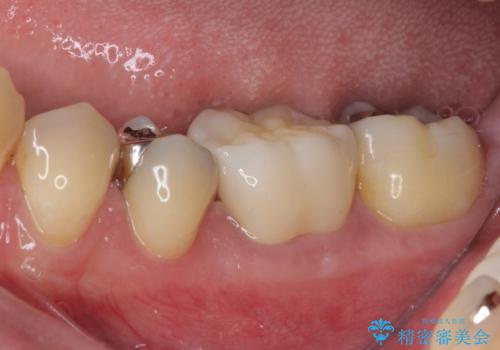

保険診療で安価に白いクラウンが入れられるということで選択されたそうですが、装着後に痛みを感じたり、ものが挟まって不快であったりと不便が多いため、セラミッククラウンにて補綴治療を行うこととしました。

自費診療は、費用が高くなりますが、よい材料を選択したり、診療時間を十分にとったりできるため、単純に白いだけではない、良質なクラウンを装着することが可能です。